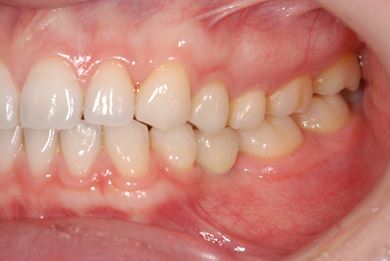

インプラントの症例写真 IMPLANT

インプラント治療

| 性別/年齢 | 女性 / 29歳 | ||||||||||||||||||||||||||||||||

| 主訴 | インプラント治療と、親知らずの抜歯の相談。なるべく安価で、短期間で終了して欲しい。 | ||||||||||||||||||||||||||||||||

| 治療方針 | 欠損部分をインプラント治療にて、機能的・審美的回復を行う。 | ||||||||||||||||||||||||||||||||

| 治療内容 | インプラント1本、メタルボンドセラミッククラウン1本 | ||||||||||||||||||||||||||||||||

| 総治療費 | 252,000円 | ||||||||||||||||||||||||||||||||

| 治療期間 | 11ヶ月 |